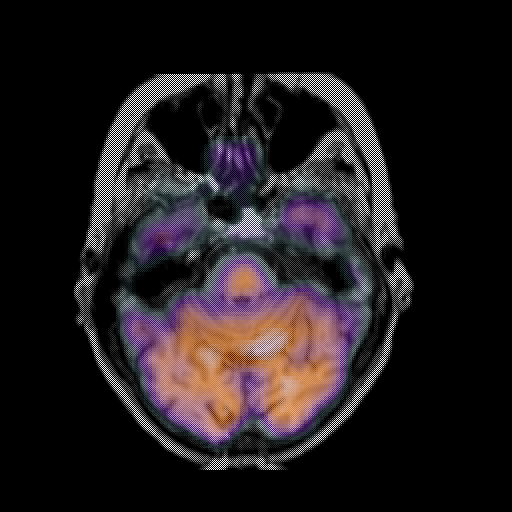

overlay: Slice 16

Slice 16

MRCBFCBF with

T1PDT2T1PDT2